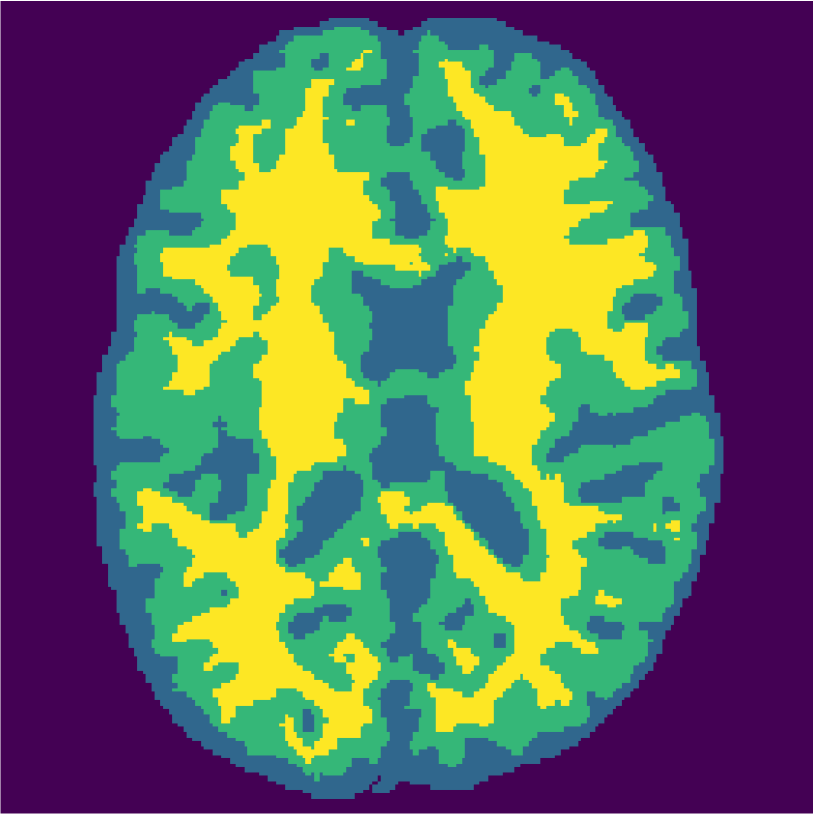

Examples of the segmentation results on one of the target test images are shown in Figure 8 for experiment 2.1, Figure 9 for experiment 2.2, and Figure 10 for experiment 2.3. Examples are shown after using 1 target patch per tissue for training, and after using 100 target patches per tissue for training. The results show that only the mrai-net classifier is able to predict a segmentation that approaches the ground truth with only 1 target patch per tissue for training (error for experiment 2.1 = 0.269, experiment 2.2 = 0.403, experiment 2.3 = 0.320), while the source and target classifiers cannot (source error for experiment 2.1 = 0.667, experiment 2.2 = 0.653, experiment 2.3 = 0.435; target error for experiment 2.1: 0.591, experiment 2.2: 0.614, experiment 2.3 = 0.596). After using 100 patches the source and target classifiers can predict a gross segmentation of WM, GM and CSF (source error for experiment 2.1 = 0.213, experiment 2.2 = 0.384, experiment 2.3 = 0.363; target error for experiment 2.1: 0.205, experiment 2.2: 0.368, experiment 2.3 = 0.368), but the mrai-net classifier prediction shows more details and a lower tissue classification error (error for experiment 2.1 = 0.111, experiment 2.2 = 0.276, experiment 2.3 = 0.284).

Figure 6 displays the manually selected patches and their position within the image. For both the source and target classifier, one target patch per tissue is insufficient to achieve good tissue classification performance (2 (top row): 0.631 and 0.613). However, the mrai-net classifier shows considerably better performance (0.223), using only one target patch per tissue. The proxy -distance also drops from near perfect separability (1.88) to near invariance (0.26). Randomly selecting (10 repeats) 1 target patch per tissue (Table 2 (bottom row)), shows worse performance of the mrai-net classifier, for both the classification error (0.250) as well as the -distance (0.41). Suggesting that purposive (information rich) sampling beats random sampling in this case.